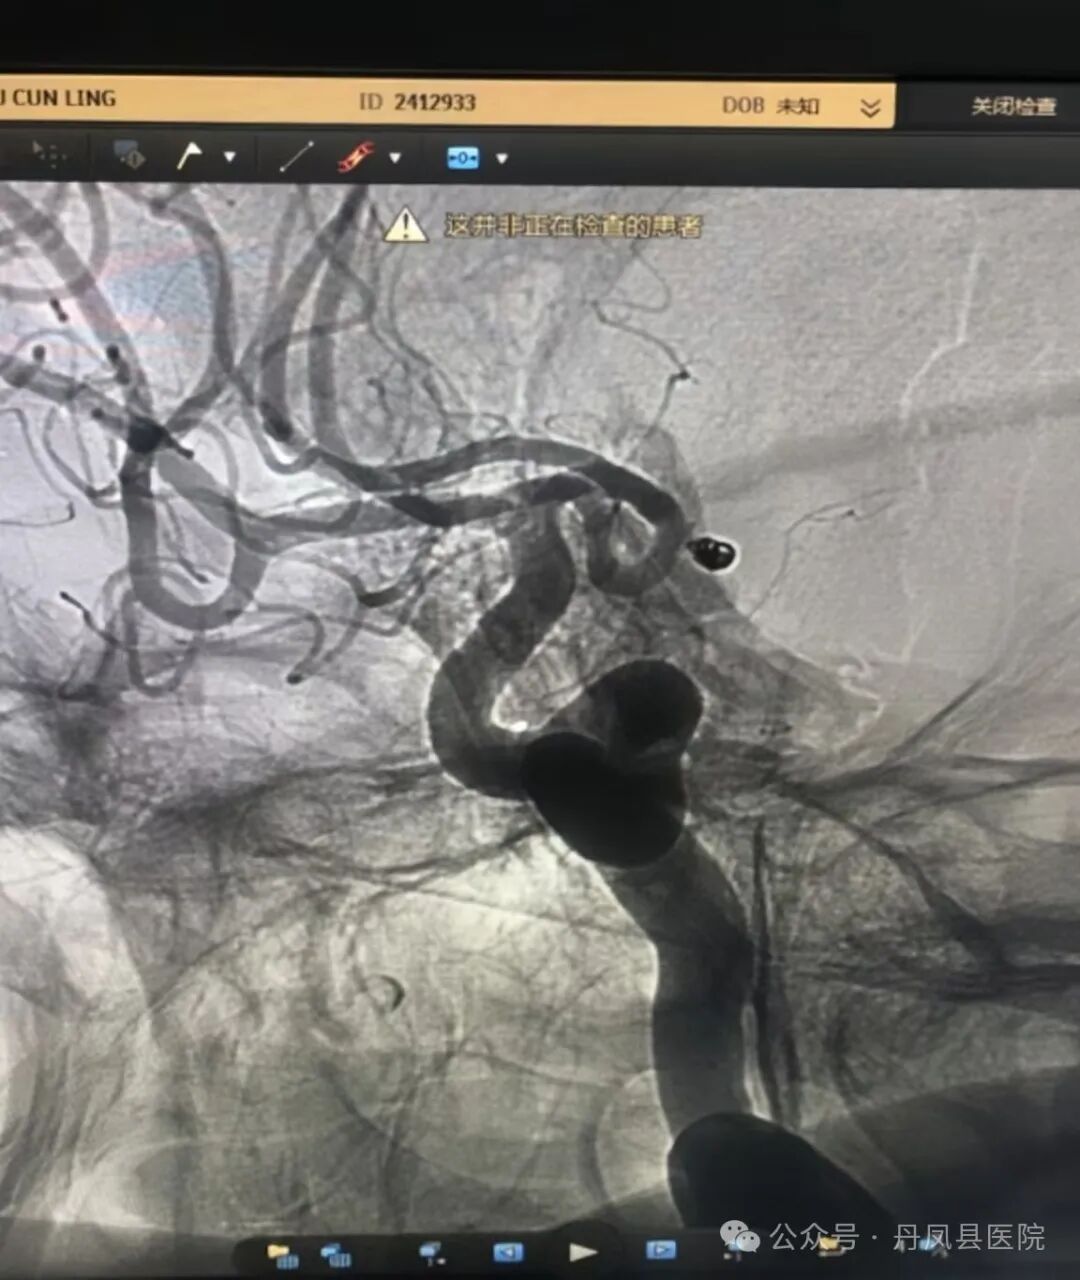

8月22日,为患者行全脑血管造影术,造影证实患者为大脑前交通动脉瘤。面对这一生命威胁,神经外科团队与患者家属进行了深入细致的沟通,详尽阐述了手术风险与医院现有的技术实力及上级医院专家支持。患者家属听后,同意在丹凤县医院接受颅内动脉瘤介入栓塞术。

图为造影发现动脉瘤8月28日,在唐都医院神经外科姜海洋教授的现场指导下,神经外科王龙珍主任、刘建锋主治医师及张永昌、赵斌轲医师联合麻醉科、介入室进行了多学科讨论,评估手术安全,最终,成功为患者实施了颅内前交通动脉瘤介入栓塞术,手术顺利,动脉瘤体被致密填塞,术后患者麻醉清醒,无神经功能受损表现。![]()